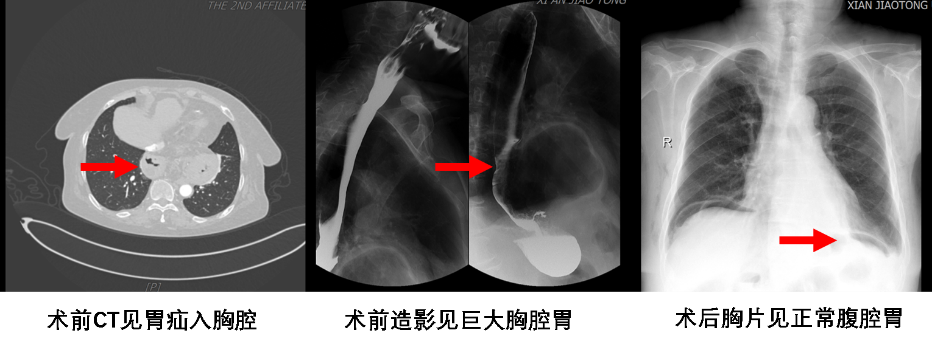

近日,一位年近8旬的老太太来到胸外科就诊,自述因反流严重,多年不能平躺入睡。如果平躺入睡,不到2小时就会因为反酸、烧心而醒来,严重影响休息。长年口服药物,症状反复。姜建涛主任详细查体了解病史后首先考虑到胃食管反流综合征,进一步通过消化道造影、胃镜等检查证实合并食管裂孔疝。该患者属于Ⅲ型食管裂孔疝,且疝囊较大,症状反复,保守治疗无效,手术指征明确。

经过我院姜建涛主任团队详细的术前评估,成功为该高龄患者行腔镜下食管裂孔疝补片修补术及胃底折叠术。手术过程中,发现患者的疝囊异常巨大,长径约10cm,且有接近一半的胃以及胃食管联合部疝入胸腔。面对如此复杂的局面,依然选择了更微创、更精细的腔镜手术。手术成功完成了疝内容物的复位、疝孔补片修补以及360°的胃底折叠术。

术后第1天复查胸片胸腔胃成功复位至腹腔,术后第3天顺利出院,患者自觉反酸症状完全消失,停药后未见症状反复发作。患者非常激动的说“熬了这么多年,终于可以平躺着睡觉了。